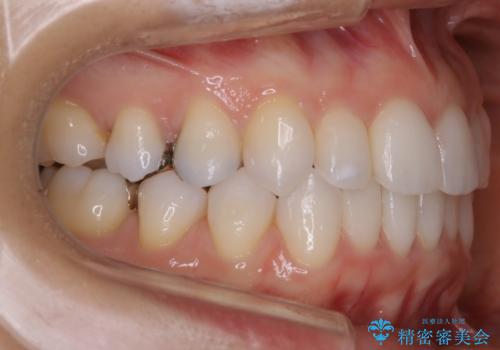

- マウスピース(インビザライン)

- 1年2ヶ月

- 5-10回